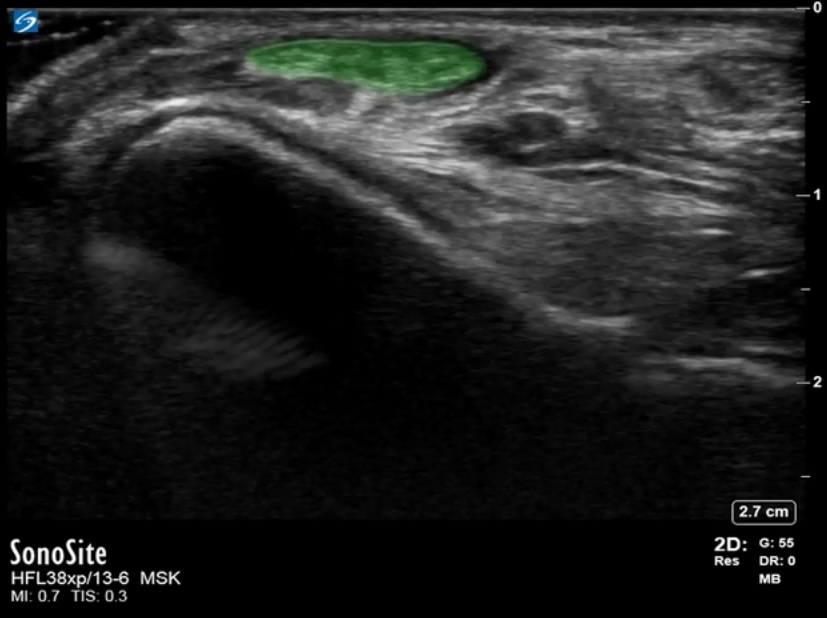

Foot & Ankle Anterior Recess Extensor Digitorum Longus Image

Highlighted Area: Extensor Digitorum Longus Tendon